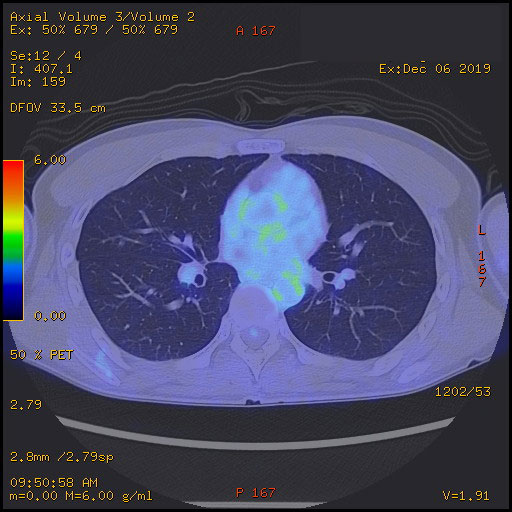

相変わらず0.1でギリ陽性を維持。 まあ上がらず横ばいなのでOKだな。 先生も全く気にしていない様子。 とはいえ「次回は9月にCTと採血ね」と抜かりなし(笑)。 2/16に採血とCT撮影をしてきた。 【4月】 時間厳守で8:15頃に核医学科を受付。 更衣室に案内されて着替え。 ロッカー開けてスリッパを見て一人爆笑(笑)。 誰もいないのでスリッパの写真を撮る。 続いて検査手順の説明を受ける。 ・投薬 ・1時間休憩 ・水分はたくさん摂ってください ・20分撮影 ・30分休憩 ・誰にも何も言わずそのまま帰ってよし とのこと。 そして静注用のライン取り。 血管が細く看護婦も悩み、少々時間を使う。 でも慎重に血管を選び抜き一発でライン確保。 さすがである。 血管にラインが入っている感覚、一瞬で抗がん剤治療時の腕の感覚が蘇るから不思議だ。 そしていきなり1時間休憩。 何も持ち込みできないので、ただただボ~ッとする。 これにも理由があって、筋肉を使うとそこに薬剤が集まってしまうらしい。 だから「何もしない」でなければならない。(と帰宅後にヨメから教わる) 体内というか細胞に薬剤が行き渡ったら20分ほどかけて撮影。 CTの機械を少々長くした程度のものだった。 気分的にもCTと同じ。 体勢は腕を横にしてきをつけの姿勢。 いつもは万歳の姿勢なので少し画像が変わりそうだ。 撮影後は30分休憩。 こちらは半減期との兼ね合いのようだ。 俺自身が放射線を出しながら街中を歩いて電車に乗るわけにはいかないということかな。 γ線エリアモニタなるものも所々に設置されている。 空間線量を計測している模様。 俺が近づいただけで0.1から12.0までどんどん上昇した。 俺自身が放射線を出しているということで、ちょっとおもしろい(笑)。 というわけで、本来であれば悪性腫瘍を疑われての検査なのだけど、あまりにも経験したことのないことばかりで、逆に楽しんでしまった(笑)。 結果は12/16。 これまたどんな画像が出てくるのかが楽しみ。